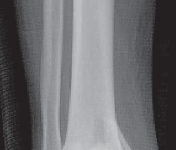

### FIG 3 • Low-energy spiral 43-A type fracture.

24. In contrast to high-energy patterns, rotational injuries ( FIG 3) cause spiral fractures of the distal tibia and fibula originating at the articular level. Intra-articular injury, if present, is typically simple and without comminution or impaction. NATURAL HISTORY